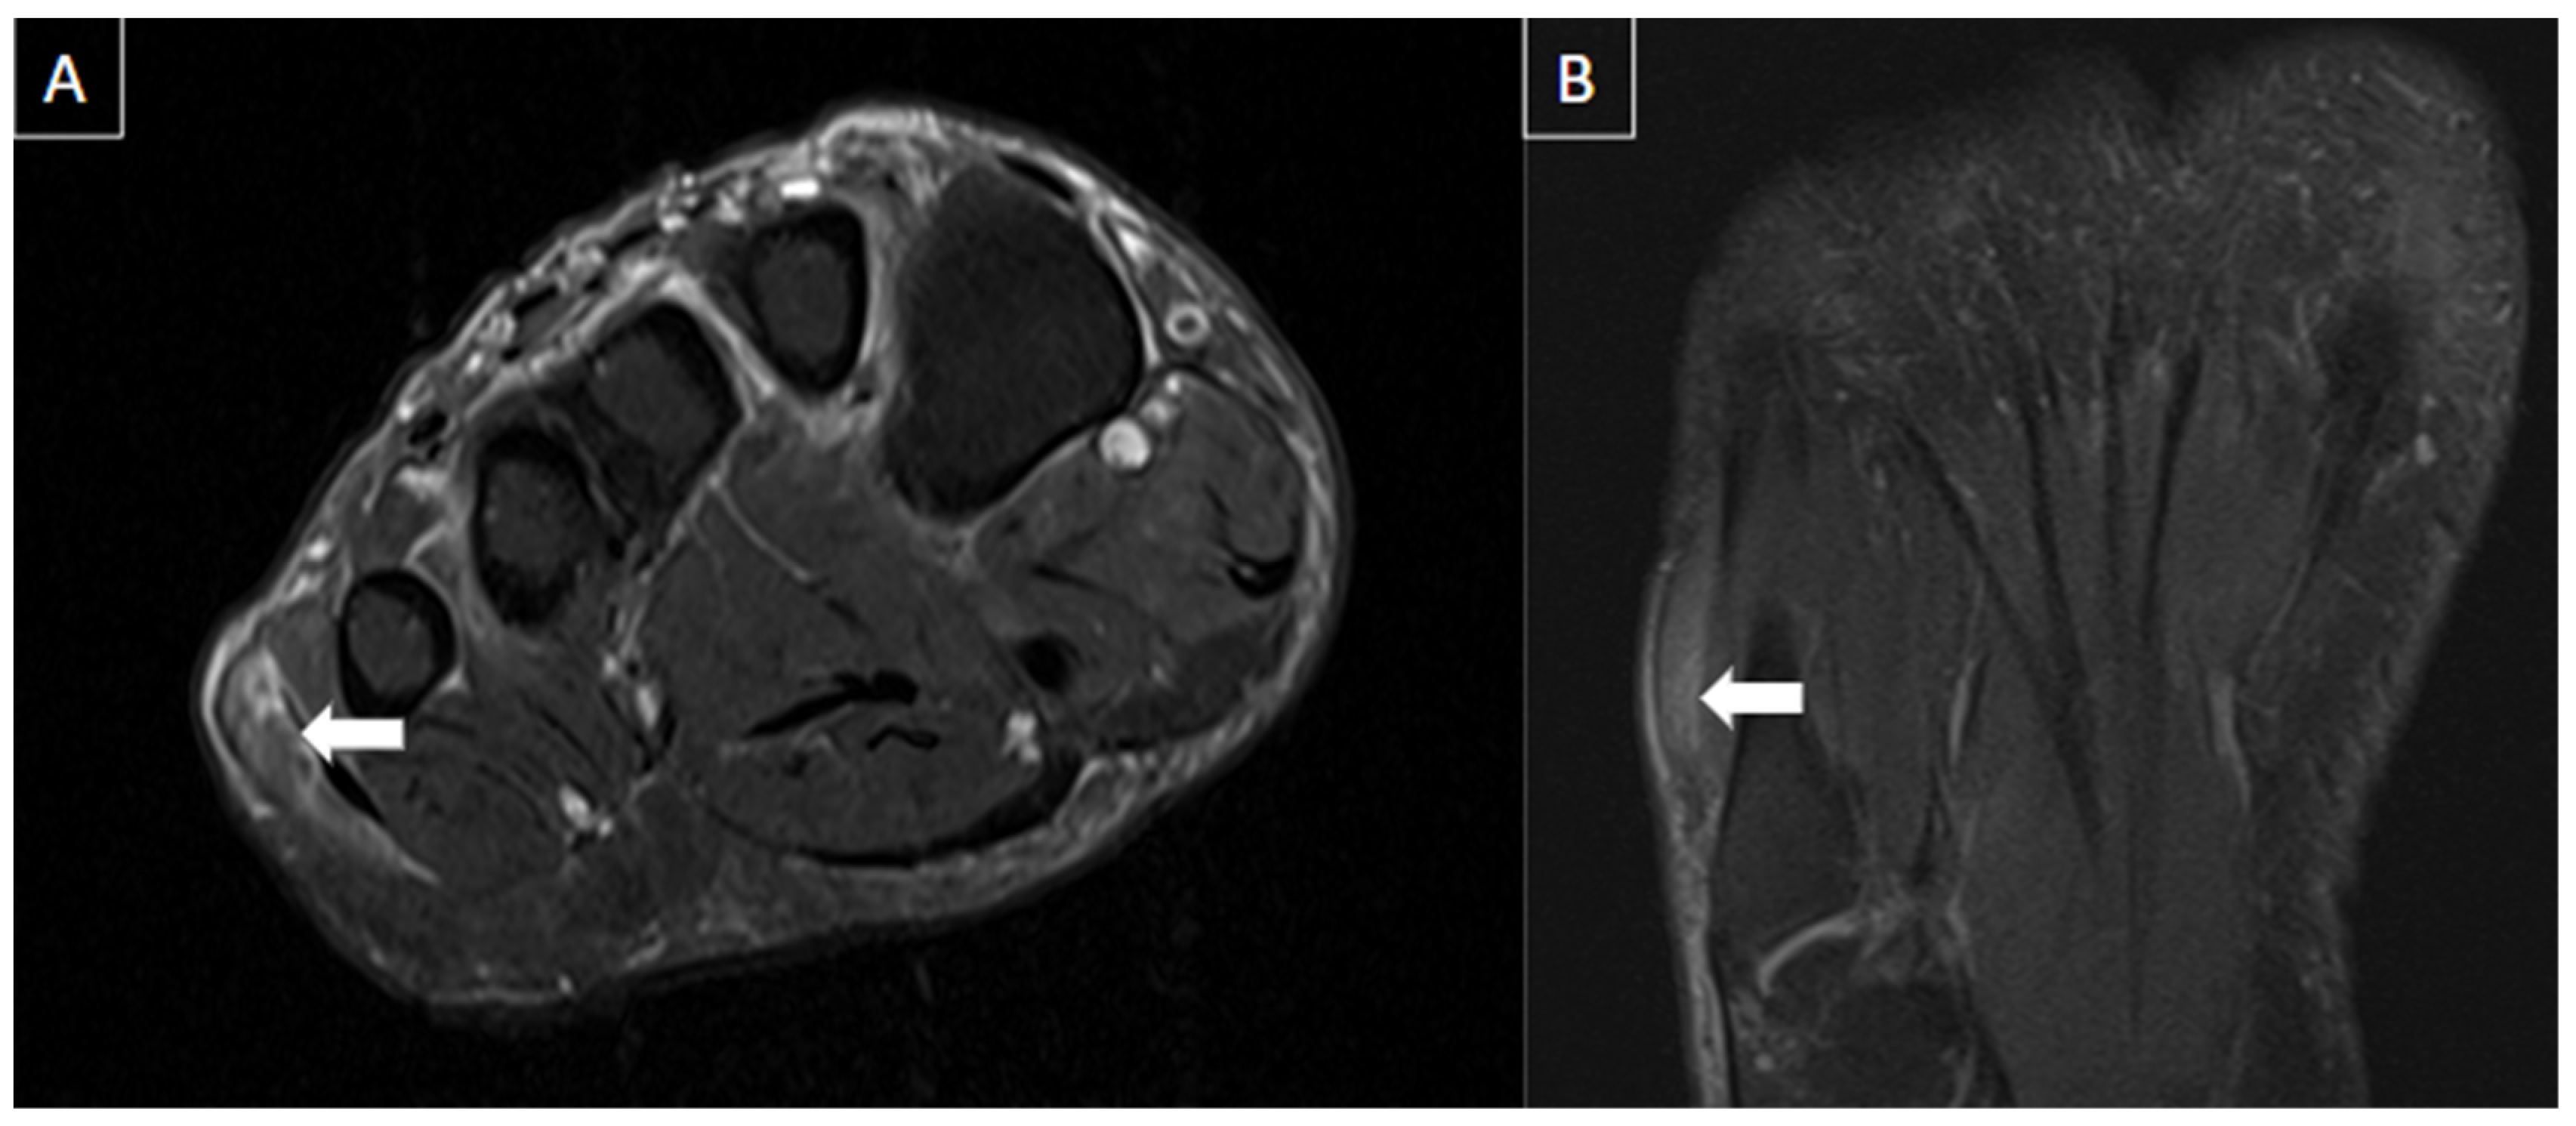

7. Complications